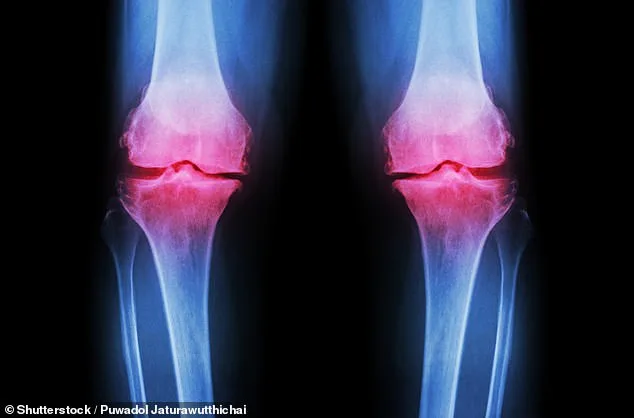

Osteoarthritis, which affects over 10 million people in the UK alone, occurs when cartilage at the ends of bones deteriorates. This leads to joint stiffness, chronic pain, and reduced mobility. Current management strategies often involve painkillers with potential side effects or lengthy physiotherapy regimens that many patients find difficult to sustain.